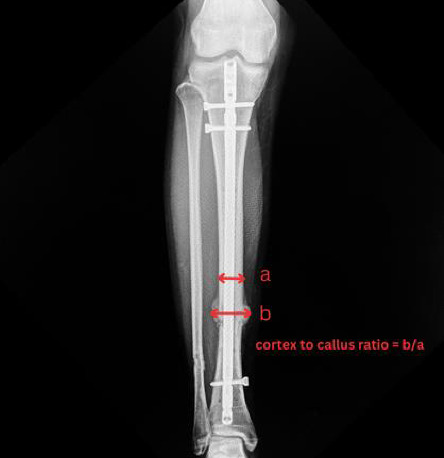

Introduction: Tibial shaft fractures, particularly those classified as AO 42-C3, represent a significant orthopedic challenge due to their high risk of delayed union or nonunion. Intramedullary nailing is a widely used treatment, though optimizing biological healing remains essential. Platelet-rich plasma (PRP), containing abundant growth factors, has been suggested as a therapeutic aid to enhance fracture healing. Methods: A randomized controlled trial was conducted, including 32 patients diagnosed with acute AO 42-C3 pure diaphyseal tibial fractures. Patients were randomized into two groups: 16 received PRP injections, while 16 received normal saline solution (NSS) injections as a control. The primary outcome, cortex-to-callus ratio, was assessed via radiographs over a 6-month follow-up. Secondary outcomes included patient-reported measures such as the SF-36 and EQ-5D-3L questionnaires and time to union. Results: The PRP group exhibited a significantly higher cortex-to-callus ratio during the third and fourth months of follow-up (p < 0.05), indicating accelerated callus formation. Moreover, the PRP group exhibited a statistically significant reduction in time to union compared with the NSS group (p < 0.05). Although other patient-reported outcomes did not show significant differences, the PRP group displayed an upward trend in SF-36 scores (p < 0.05). Discussion: PRP significantly enhances midstage fracture healing in tibial shaft fractures, as evidenced by improved callus formation and reduced time to union. These results indicate that PRP holds promise as a therapeutic adjunct for managing tibial fractures. Additional studies with larger sample sizes and diverse fixation techniques are needed to validate these findings and further assess the broader potential of PRP in orthopedic practice.